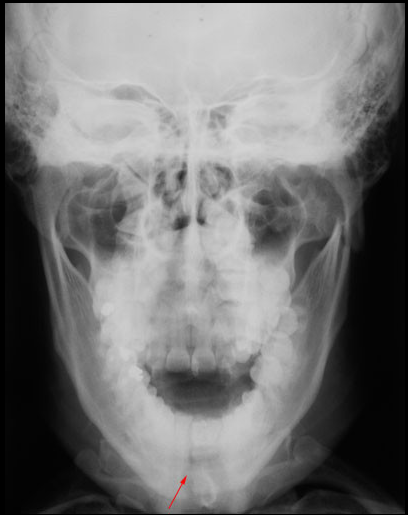

Paciente de 32 años acude a la consulta radiológica post accidente automovilístico por presentar múltiples contusiones. Al examen extraoral el paciente refiere dolor a la palpación de la región mentoniana, asi como de la zona geniana del lado izquierdo, presentando limitación a la apertura. En la radiografía panorámica (fig.1) podemos observar un trazo de fractura de forma vertical localizada en la sinfisis mentoniana que va desde el reborde alveolar hasta la basal mandibular, ademas de una linea radiolúcida de forma oblicua localizada a nivel subcondilar del lado izquierdo. En la radiografía posteroanterior tipo Towne (fig.2) nótese un desplazamiento hacia medial del cóndilo mandibular del lado izquierdo, y en la radiografía oclusal (fig.3) confirmamos el trazo de fractura en la sinfisis mentoniana con desplazamiento de segmentos.